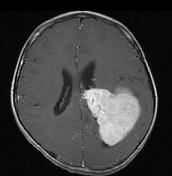

问题 男,8岁,头痛伴呕吐,左侧眼视物不适5天,请根据所提供图像,选择最可能的诊断()

选项 A.(左侧脑室)脑膜瘤 B.(左侧脑室)室管膜瘤 C.(左侧脑室)脉络丛乳头状瘤 D.(左侧脑室)胶质瘤 E.(左侧脑室)少突胶质细胞瘤

答案 C